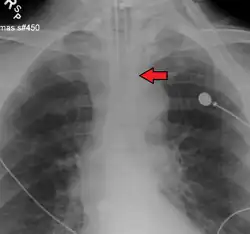

Ideally, at least one of the methods utilized for confirming tracheal tube placement will be a measuring instrument. Waveform capnography has emerged as the gold standard for the confirmation of tube placement within the trachea. Other methods relying on instruments include the use of a colorimetric end-tidal carbon dioxide detector, a self-inflating esophageal bulb, or an esophageal detection device.[35] The distal tip of a properly positioned tracheal tube will be located in the mid-trachea, roughly 2 cm (1 in) above the bifurcation of the carina; this can be confirmed by chest x-ray. If it is inserted too far into the trachea (beyond the carina), the tip of the tracheal tube is likely to be within the right main bronchus—a situation often referred to as a "right mainstem intubation". In this situation, the left lung may be unable to participate in ventilation, which can lead to decreased oxygen content due to ventilation/perfusion mismatch.[36]